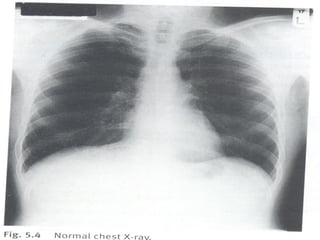

Imagem

Radiografia simples de tórax

- Póstero-anterior

Ausculta pulmonar

 Aquele que se inicia na ausculta do aparelho

respiratório deve, necessariamente, se

submeter a um treinamento exaustivo,

ouvindo inúmeras vezes um pulmão normal.